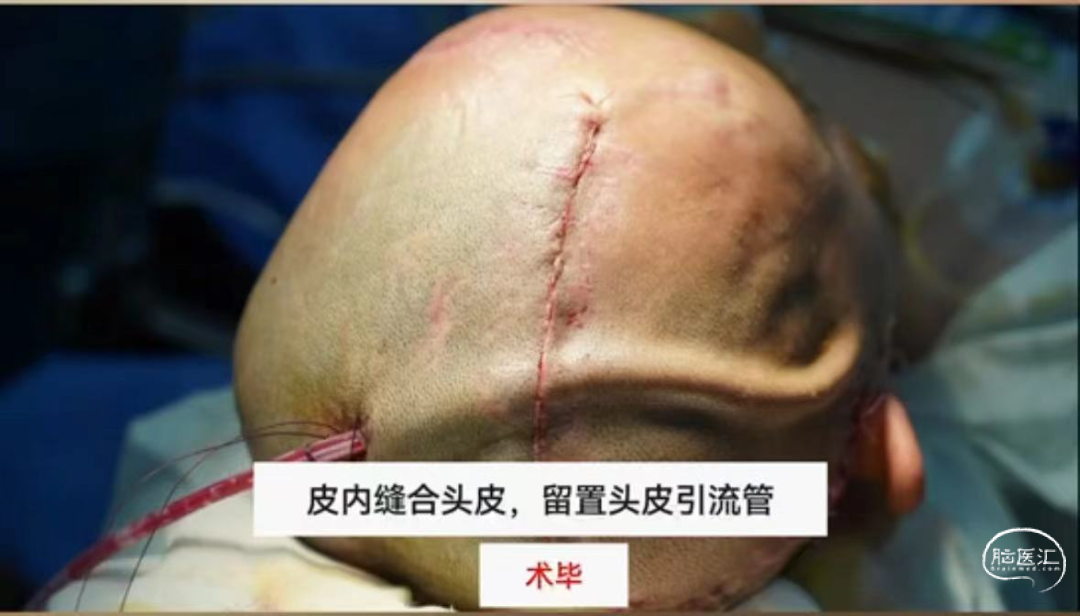

步骤四:放置引流管,彻底止血后进行头皮缝合

术后第1天

保护切口血运

严格经原切口切开头皮

尽量减少头皮夹的使用和电烧切口缘的渗血

耳屏前切口注意保护颞浅动脉

头皮缝合可采取皮内缝合